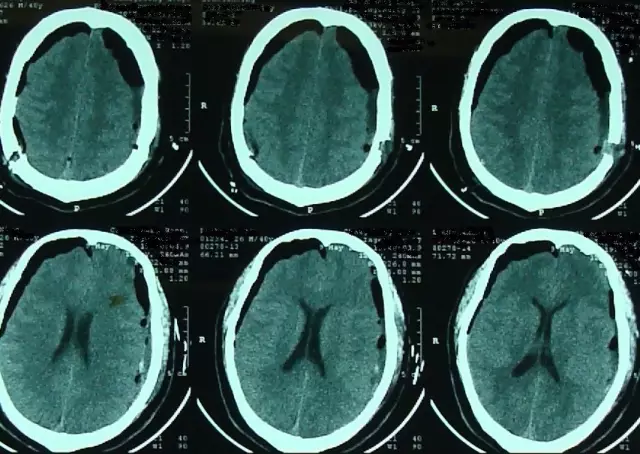

2017年5月7日上海某医院头颅CT提示:颅脑术后,双侧额颞顶部硬膜下积液积血(图4)。于2017年5月9日行双侧钻孔引流术,2017年5月12日头颅CT提示:钻孔术后改变,颅内积气(图5)。患者术后头痛症状持续加重,出现意识不清,5月15日再次复查头颅CT提示脑肿胀明显(图6),于5月17日再次行右侧硬膜下血肿清除+左侧硬膜下血肿钻孔引流术,术后患者出现脑疝,于2017年5月21日行右侧额颞顶扩大去骨瓣减压术+血肿清除术。(图7)

图7. 2017年5月22日外院头颅CT提示:右侧额颞顶部去骨瓣术后改变。

图8. 2017年7月4日本院头颅CT提示:右侧额颞顶部去骨瓣术后改变,脑室扩张。